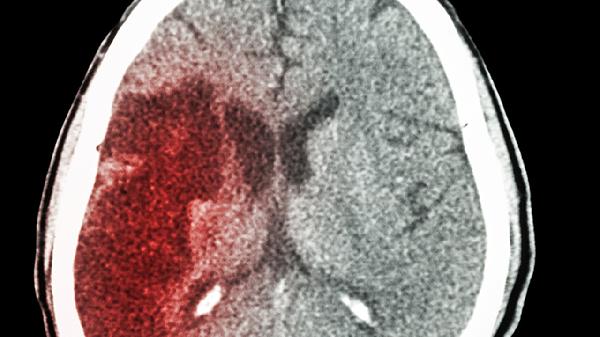

50岁后警惕脑梗信号!上半身这4个异常别忽视,可能是血管在求助

50岁就像人生的分水岭,身体开始悄悄拉响警.报。那些被误以为是"年纪大了都这样"的小毛病,可能是血管发出的求.救信号!特别是上半身这几个不起眼的异常,千万别当成普通衰老现象。

这些信号有时转瞬即逝,很容易被忽视。建议50岁以上人群每半年做一次颈动脉超声,有"三高"病史的更要缩短至3个月。记住,预防永远比治疗更重要!现在就去检查下自己和家人的身体状态吧,血管健康才是长寿的基石。